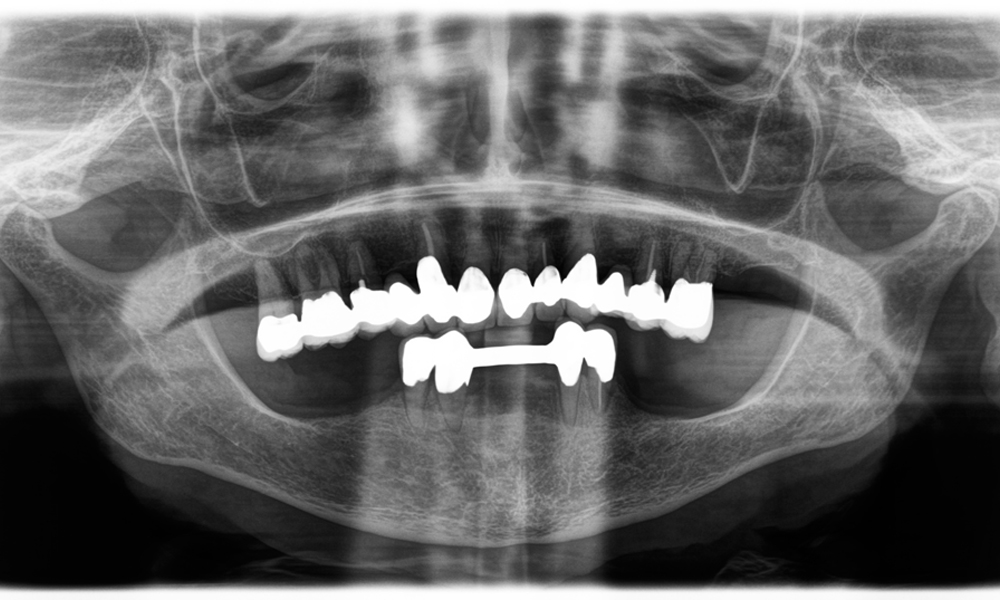

Вторият случай, който подчертава клиничните възможности на Power Edition е свързан с подмяната на увредена циркониева корона при 63-годишна пациентка. Пациентката беше с отчупена фасета на 20-годишната си циркониева корона на зъб 6. Въпреки че дефектът беше в задната област, пациентката намираше дефекта за притеснителен и поиска нова реставрация.

Power Edition позволи прецизно разрязване, като увеличеният въртящ момент и подобреното охлаждане допринесоха за контролираното отстраняване на короната без значителна загуба на материал. Системата на цангата и повишеният въртящ момент се оказаха от съществено значение в този процес.